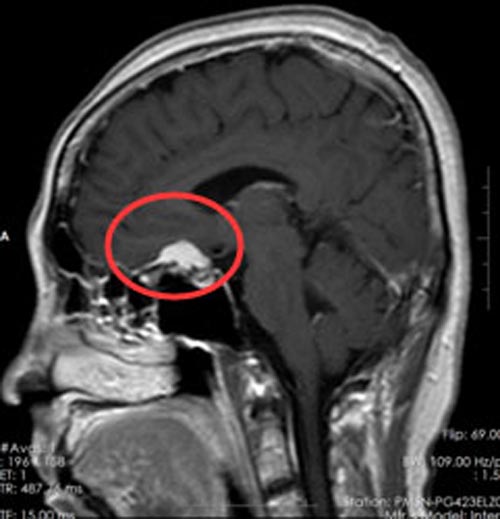

近2个月病情有加重趋势,并伴有头痛症状,当地医院行CT检查,结果示:鞍区占位。广东三九脑科医院头颅MR提示:1.鞍区巨大型占位性病变,肿瘤大小约2.1cm×1.9cm×1.1cm。2.梗阻性脑积水。陈姐及家人都同意手术治疗,由综合神经外科科鲁明副院长主刀行“鞍区巨大型占位性病变切除术”,手术顺利,术后病理示:鞍区脑膜瘤。术后经过一段时间的抗感染、脱水、营养神经、对症支持治疗后,陈姐恢复很好,视力较术前好转,重影症状消失。

▲手术前